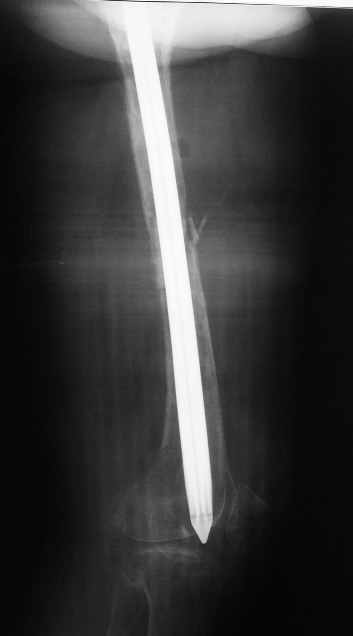

По просьбе коллег выношу на обсужение следущий случай лечения перелома бедра,

о дальнейшем лечении больной 48 лет с РПА. Анамнез: В 2005 году в ЦРБ - остеосинтез перелома

бедра пластиной. В 2007 г. воспаление в ср. трети бедра и удаление пластины. Через 2 мес. -

рефрактура и фиксация гвоздем "фикшн". Через 2 мес. после синтеза - свищ, "функционирующий"

по настоящее время. Что делать? Если бы вопрос задавался лично мне, то я бы предложил удаление

существующего фиксатора, санацию костномозгового канала, установку спейсера на тонком

сплошном титановом гвозде с последущей заменой на полноценный сплошной титановый гвоздь.

Правда, что делать с отверстием в колено, вернее как провести санацию так чтобы

минимизировать риск распространения инфекции в коленный сустав, представляется не очень